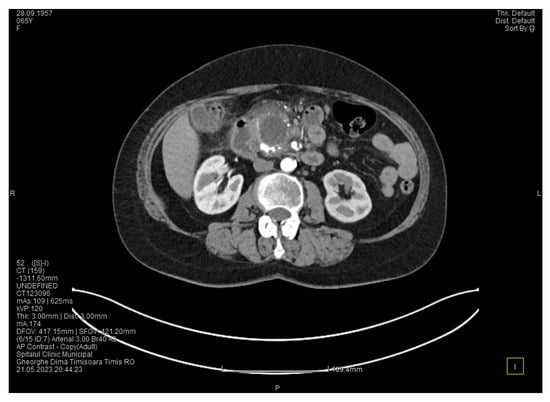

Laboratory tests showed a serum lipase level more than 10 times above the upper normal range. The contrast-enhanced computed tomography (CT) showed multiple calcifications in the pancreatic tissue, dilatation of the main pancreatic duct measuring approximately 12.5 mm (Figure 1), a non-iodophilic intraparenchymal cyst in the head of the pancreas measuring 23/25 mm, which was associated with acute inflammation (Figure 2), and densification of the peripancreatic fat, which was more intense at the head of the pancreas. In addition, enlarged pericephalic and periaortocaval lymph nodes were observed. There were no changes in the liver or the gallbladder, only a mild ectasia of the intrahepatic bile ducts, and no dilatation of the common bile duct. Other changes included multiple atheromas of the abdominal aorta. The symptoms, the lab results, and the CT findings led to the diagnosis of acute pancreatitis.

Figure 1. The initial CT scan shows a dilated Wirsung duct and calcifications in the pancreatic tissue.